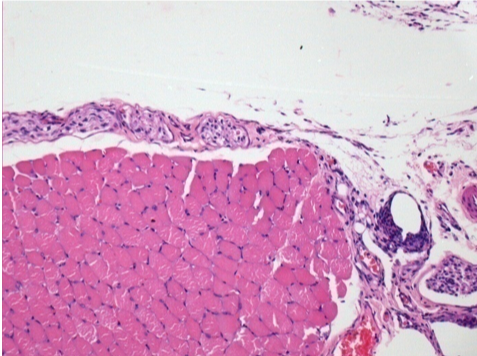

Sağ deri altı pretibial bölgede 0.5 ml (5x 0.1ml) Endopeel SC Enjeksiyonu.

Sol:200x-Kontrol-SC

R-D10-SC-200X